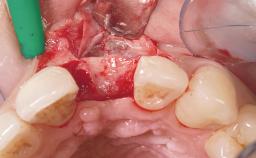

Late Placement of an Implant in a Maxillary Left Central Incisor Site

Bone Augmentation Horizontal|Staged

Augmentation Materials Xenogenous|Membrane

Bone Volume Deficient horizontally, requiring prior grafting